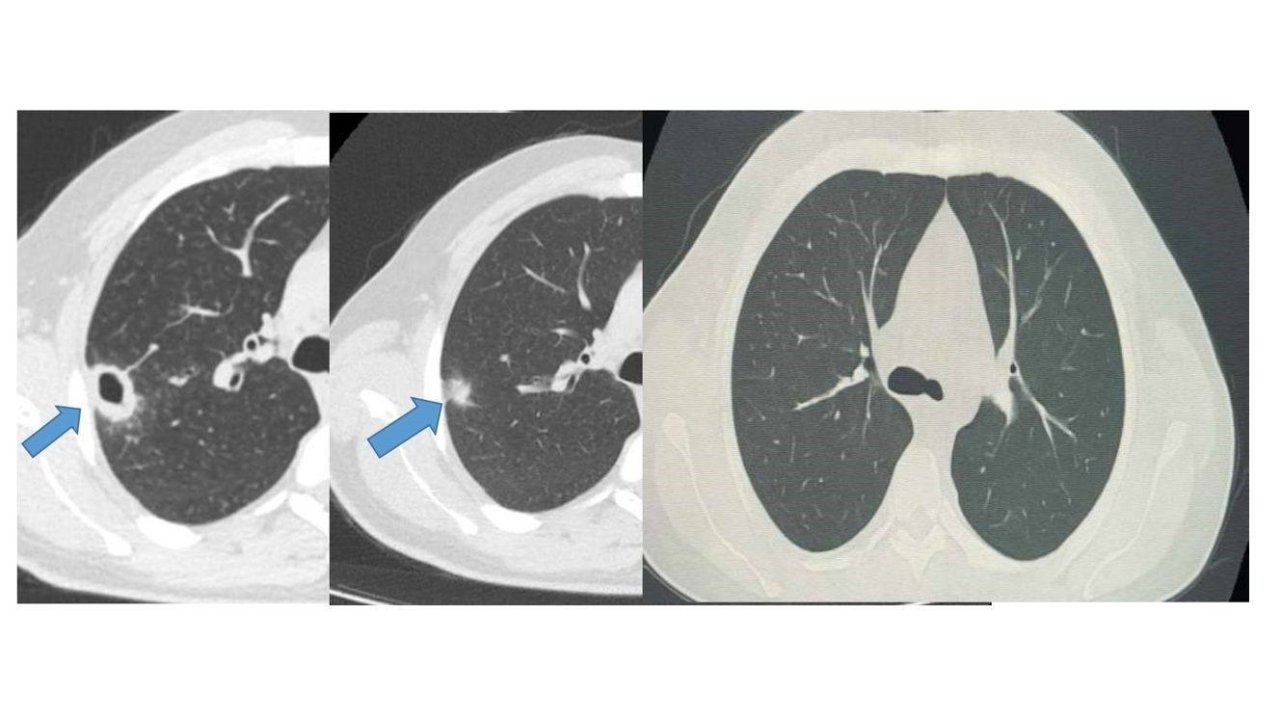

Bayburt Devlet Hastanesine öksürük ve balgam şikayetiyle başvuran 50 yaşındaki hastanın akciğerinde kitle benzeri bir doku tespit edildi. Yapılan tetkikler sonucu ciddi bir hastalık olmadığı belirlenen hasta, erken tanı ve doğru tedavi sayesinde sağlığına kavuştu.

Göğüs Hastalıkları Uzmanı Uzm. Dr. Hilal Sayma tarafından muayene edilen hastaya ileri tetkik amacıyla bronkoskopi işlemi uygulandı. Bronkoskopi sonucunda lezyonun kanser veya tüberküloz gibi ciddi hastalıklarla ilişkili olmadığı belirlenerek, hasta için uygun tedaviye başlandı.

İki haftalık tedavi sürecinin sonunda yapılan kontrollerde lezyonun neredeyse tamamen gerilediği görüldü. Sağlığına kavuşan hastanın taburcu edildiği ve durumunun iyi olduğu öğrenildi.